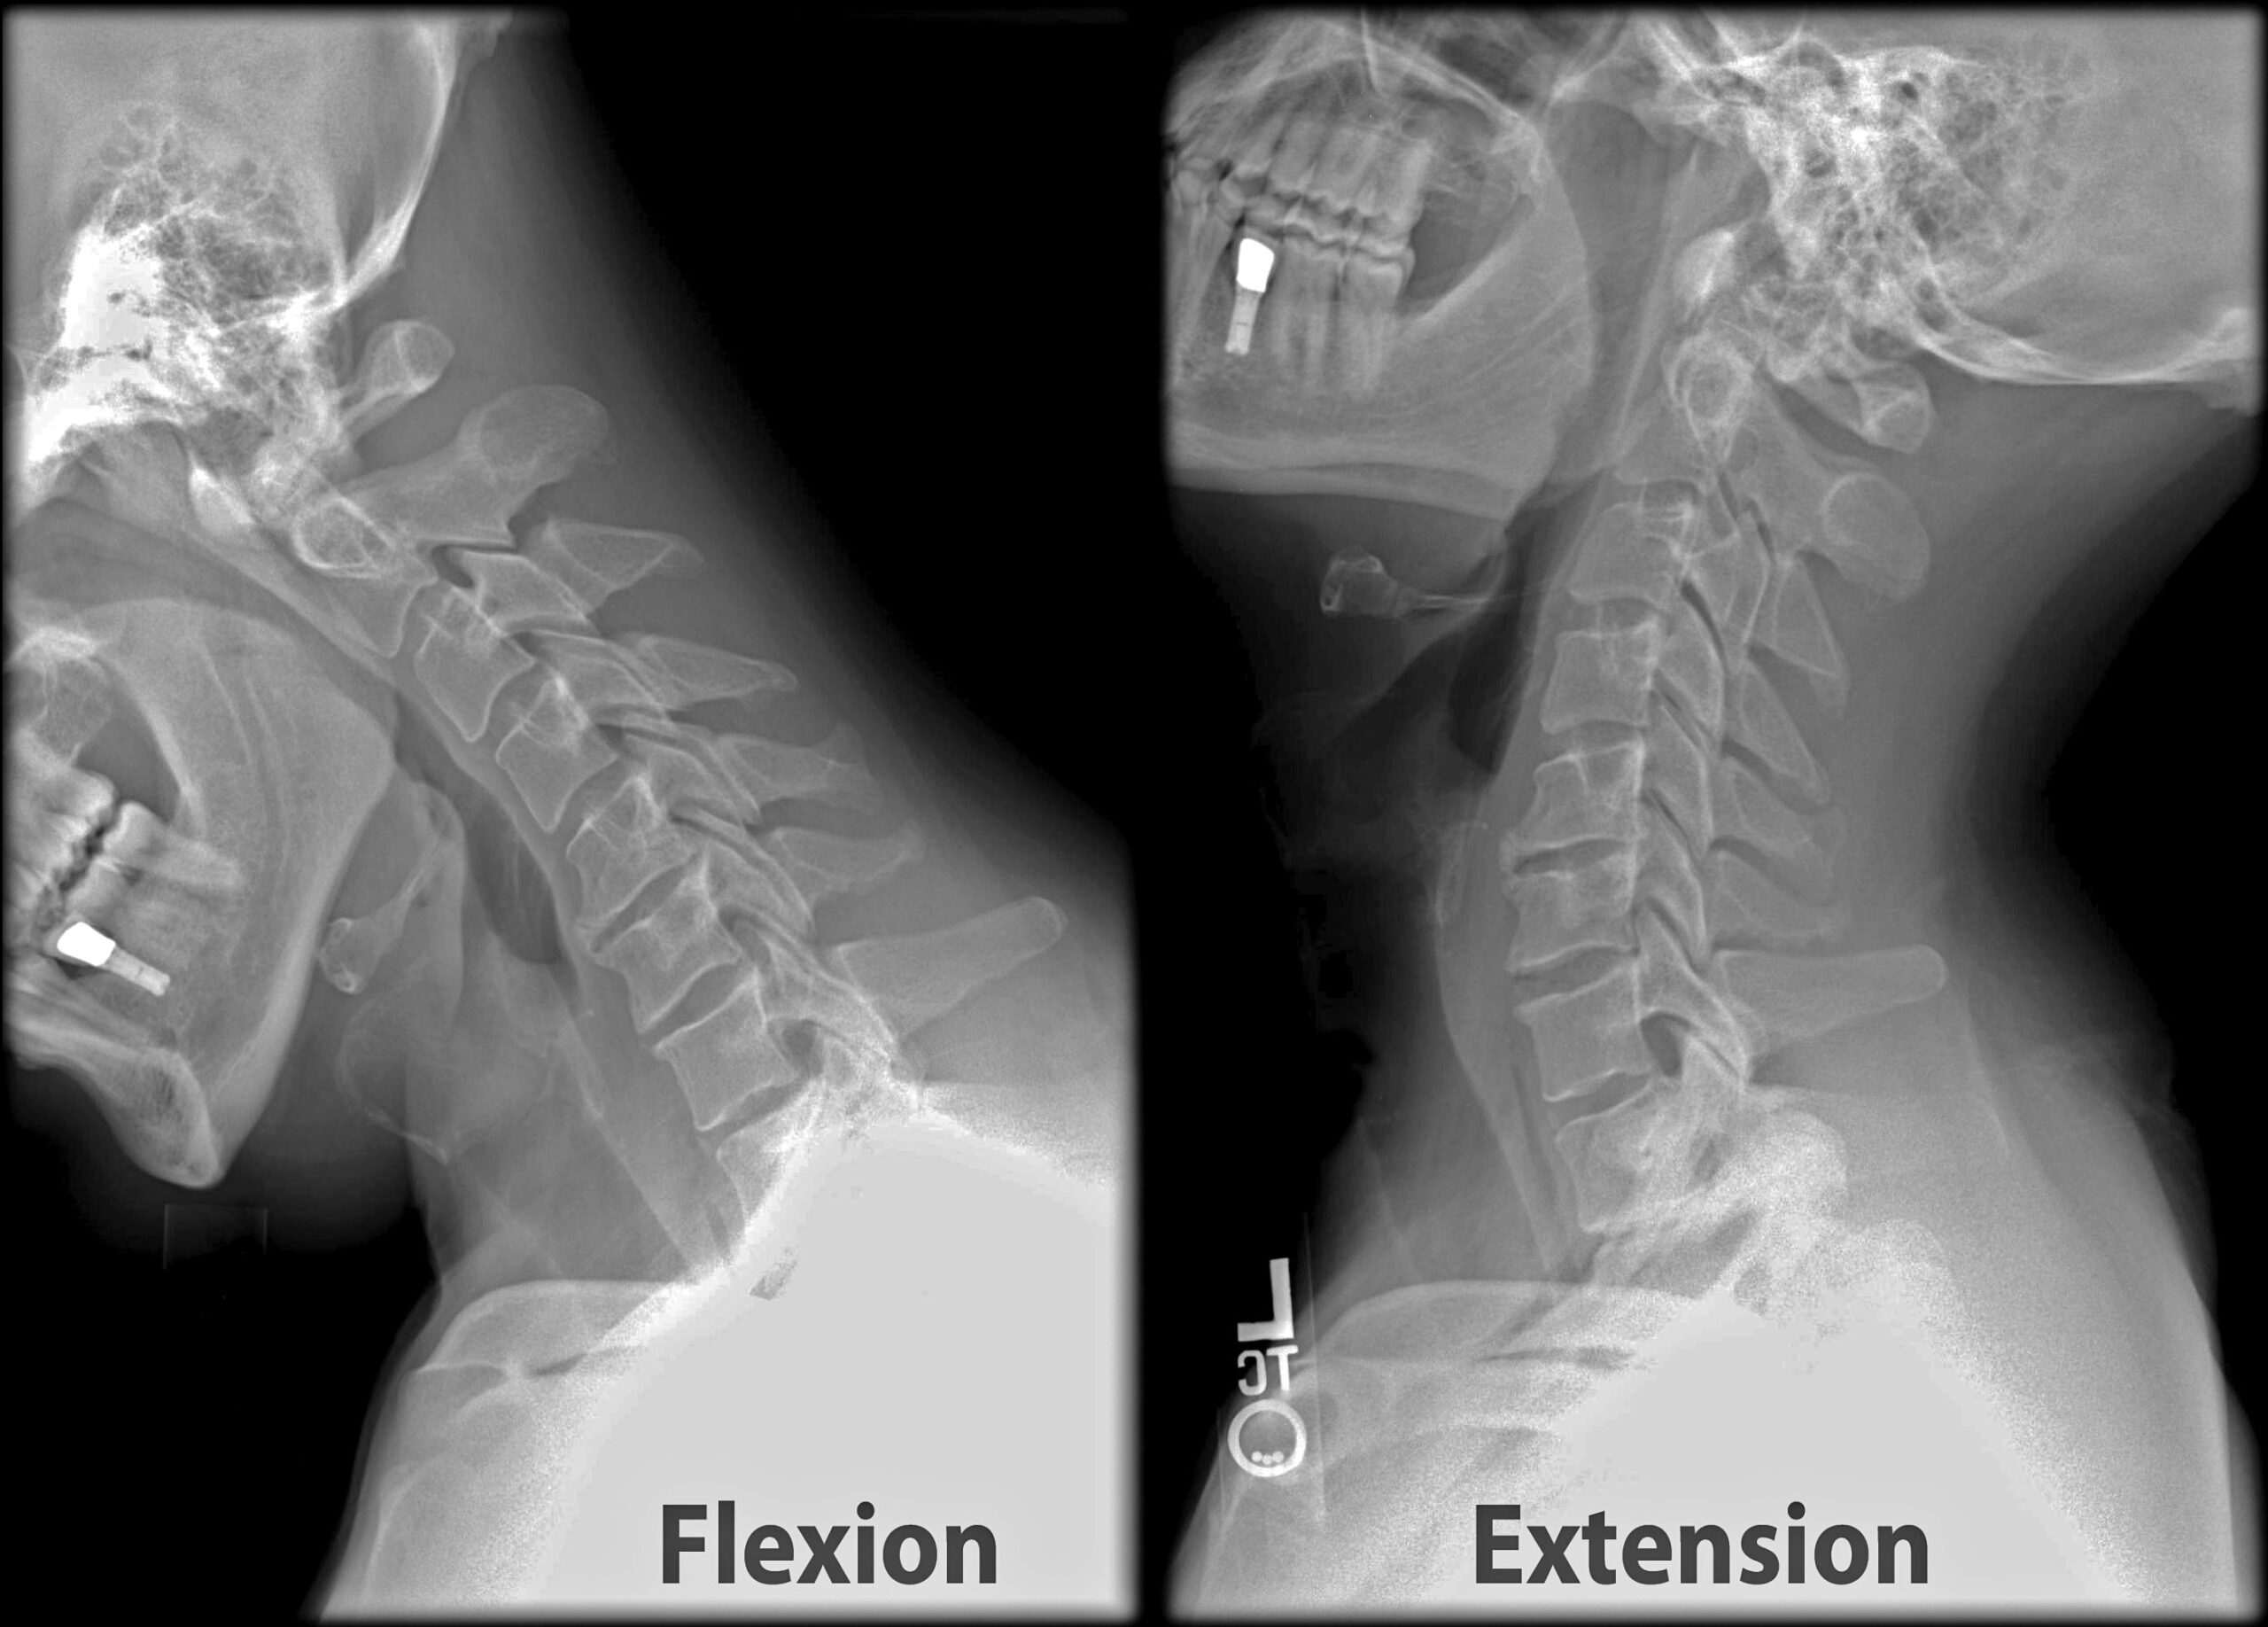

В случая с врата ни имаме няколко групи стави, наречени фасетни стави. Те са разположени от всяка страна на врата. Когато изщракваме врата си, фасетните стави се разтягат, което позволява на течността да се разпространи в ставната капсула. След като течността се превърне в газ, ставите на врата издават характерния си звук. И точно това е, което кара процесът по изпукване на врата да ни дава усещането за освобождаване на натиска в тази област.